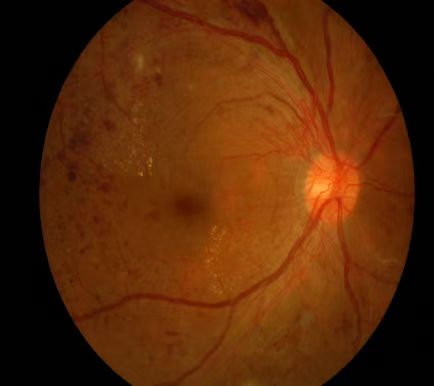

不同程度的糖尿病视网膜病变